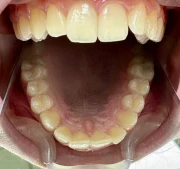

Стрипинг

Serviciul a fost efectuat la Дентално студио ТОП ДЕНТАЛ de томи пелова pe 9 Okt., 25

София, жк. Младост 1, бул. „Андрей Сахаров“ 11, търговски комплекс “Рея”,ет.2, България